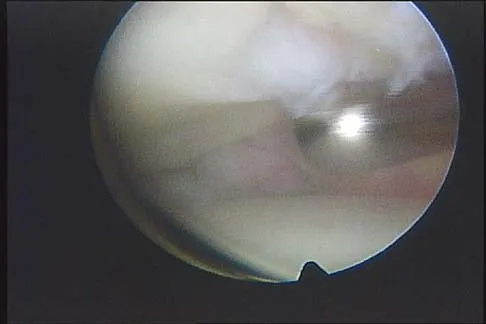

A 31-year-old woman has increasing pain and tightness in her right knee, with occasional stiffness and recurrent hemorrhagic effusions. MRI scans are shown in Figures 2a and 2b. What is the most likely diagnosis?

Explanation

PVNS is a rare inflammatory granulomatous condition of unknown etiology, and causes proliferation of the synovium of joints, tendon sheaths, or bursa. The disorder occurs most commonly in the third and fourth decades but can occur at any age. MRI provides excellent delineation of the synovial disease. Characteristic features of PVNS on MRI include the presence of intra-articular nodular masses of low signal intensity on T1- and T2-weighted images and proton density-weighted images. Synovial biopsy should be performed if there is any doubt of the diagnosis. Total synovectomy (open or arthroscopic) is required for the diffuse form, although recurrence is common. Rheumatoid arthritis and synovial chondromatosis are not typically associated with hemorrhagic effusions. De Ponti A, Sansone V, Malchere M: Result of arthroscopic treatment of pigmented villonodular synovitis of the knee. Arthroscopy 2003;19:602-607. Chin KR, Barr SJ, Winalski C, et al: Treatment of advanced primary and recurrent diffuse pigmented villonodular synovitis of the knee. J Bone Joint Surg Am 2002;84:2192-2202.